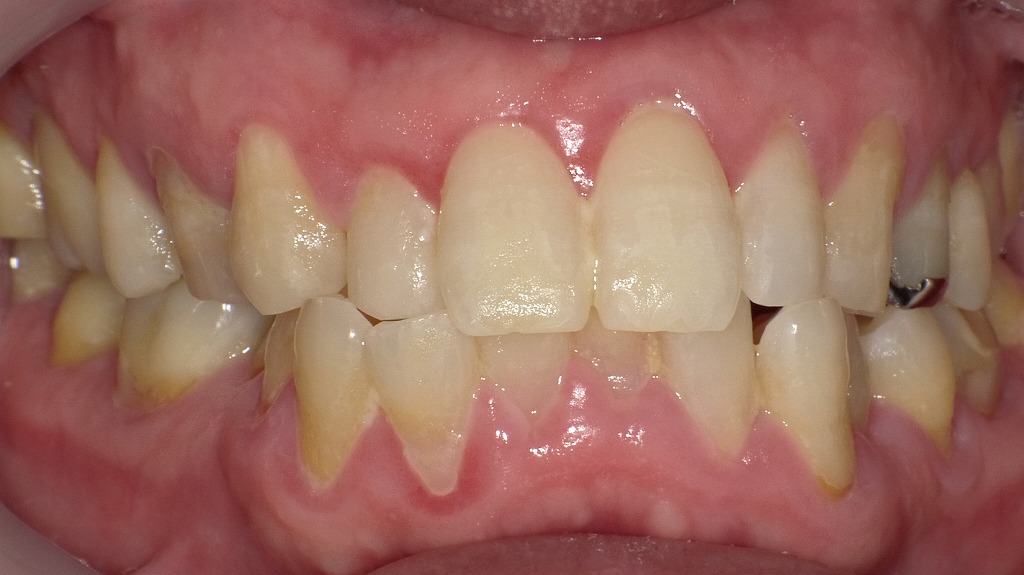

磨き残しが炎症を引き起こした症例

前歯から奥歯の歯肉にかけて赤み・腫れがみられ、歯肉炎の典型的な所見を示しています。歯と歯ぐきの境目に付着したプラーク(歯垢)が炎症の主な原因で、適切に除去されないと出血・腫脹・発赤が進行します。毎日の丁寧なブラッシングと定期的なクリーニングが、健康な歯ぐきを保つために重要です。

🔸【若年者の前歯の歯肉炎について】

🦷【症状1】自然出血が見られる

- 前歯の歯ぐきから、特に何もしていなくても自然に出血が見られます。

- 出血部位は2番(側切歯)と犬歯の間が中心で、比較的多量の出血が確認されています。

🪥【症状2】歯磨き時の出血

- 歯ブラシをあてると、非常に容易に出血します。

- 少しの刺激でも出血することから、歯肉に強い炎症が起こっていると考えられます。

💡【補足】考えられる原因と対応

出血が続く場合は、早めに歯科を受診し、プロによるクリーニングやブラッシング指導を受けることが大切です。

プラークの蓄積や不十分なブラッシング、**ホルモンバランスの変化(思春期)**が原因のことも。

🔸【成人の下顎前歯に見られる歯肉炎】

🦷【症状1】下顎前歯の歯ぐきからの出血

- 下の前歯全体の歯ぐきに、軽度ながら出血が確認されています。

- 特に、歯ぐきの色調変化やわずかな腫れを伴っている可能性があります。

🔍【症状2】歯と歯の間から自然出血

- ブラッシングをしていない状態でも出血しており、これは自然出血と呼ばれます。

- 主に**歯間部(歯と歯の間)**に炎症が集中していることが考えられます。